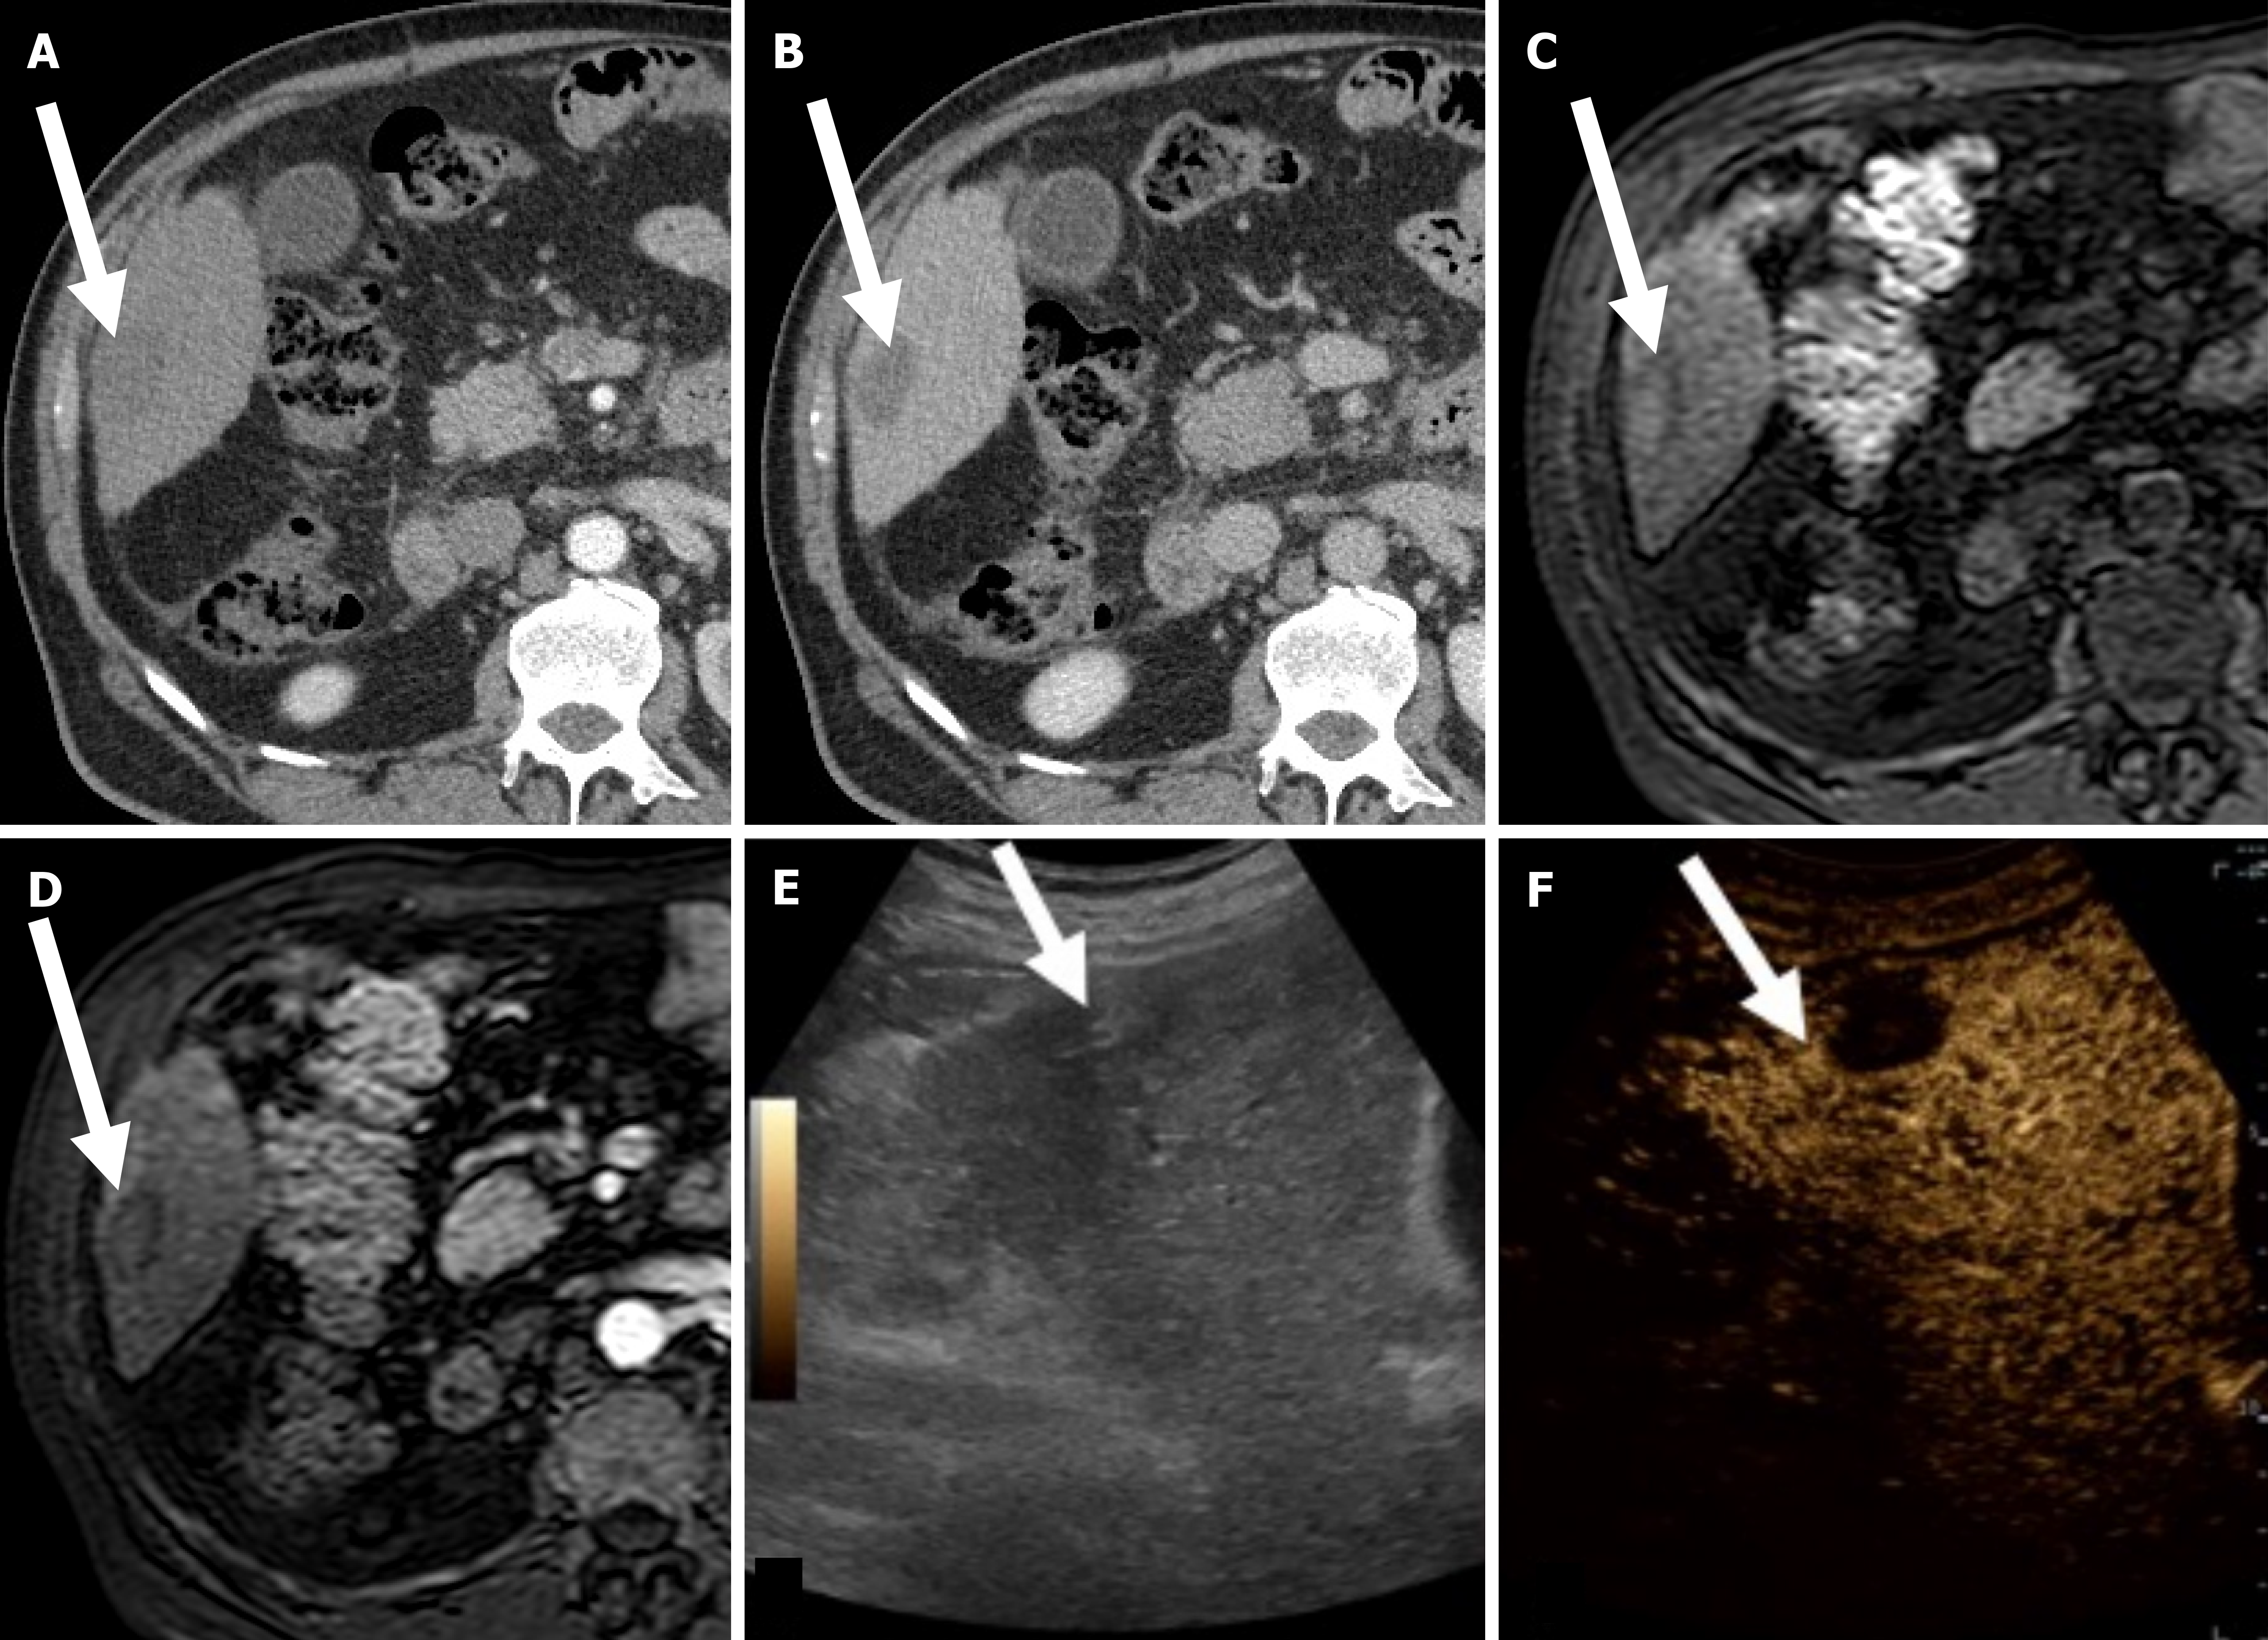

Figure 1 Successful hepatocellular carcinoma radiofrequency ablation in a 69-year-old woman with hepatitis C virus-related cirrhosis.

A: On computed tomography obtained 1 month after radiofrequency ablation (RFA) the treated area (arrow) is slightly hyperattenuating on unenhanced phase due to coagulative necrosis; B: On corresponding hepatic arterial phase (HAP) the treated area shows no enhancement; C: On magnetic resonance imaging (MRI) obtained 2 months after RFA the treated area is slightly hyperintense on unenhanced T1-weighted image due to coagulative necrosis; D: On corresponding HAP the treated area shows no enhancement; E: On gray-scale ultrasound image obtained immediately after MRI the treated area is heterogeneously and slightly hyperechoic (arrow); F: Corresponding contrast enhanced ultrasound image achieved 18 seconds after injection shows no a hyperenhancement (arrow).